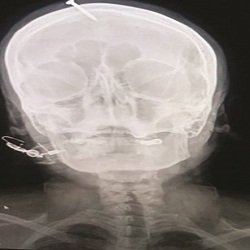

معالج يُدخل مسمارا في رأس امرأة من أجل إنجاب صبي

بعدما فشلت في نزع المسمار من رأسها بنفسها، توجهت امرأة باكستانية حامل بمولود أنثى، ولديها ثلاث بنات غيرها، إلى المستشفى في مدينة بيشاور، شمال غربي البلد، لتتخلص من المسمار الذي أدخله معالج في رأسها، بعد أن أكد لها أنه بذلك ستضمن المرأة إنجابها مولوداً ذكراً.

الطبيب حيدر خان لفت إلى أن المرأة كانت في كامل وعيها عند حضورها إلى المستشفى، إلا أنها كانت تعاني كثيراً.

وفي صورة تم التقاطها بالأشعة السينية لرأس المرأة، تبيّن أن المسمار اخترق الجمجمة بخمسة سنتيمترات.